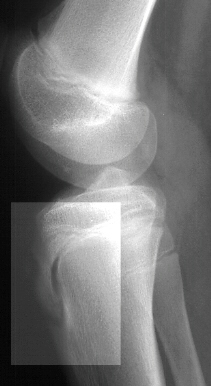

This 11 year old female presented to Orthopaedic Clinic complaining

of right knee pain . There was no history of trauma. This pain

increased with activity and decreased at rest and had been present

for approximately one year. A past history of osteomyelitis of

the right tibial shaft at age two was elicited. This infection

was treated with IV antibiotics and the child had no problems

until the recent symptoms started one year ago. When asked to

localize the pain the patient pointed directly to the tibial tubercle.

Prominence of the right tibial tubercle was noted as compared

to the left.. The tibial tubercle was warm, slightly red, swollen

and tender to palpation. There was pain with resisted knee extension

but no pain to passive knee range of motion. There was no joint

line tenderness or effusion. The right knee had full range of

motion with no hamstring or quadriceps tightness. There was no

instability to varus or valgus stress. Lochman and MacMurray tests

were negative. There was no pain to palpation over the infrapatellar

ligament and patellar tracking was normal. An x-ray was obtained.